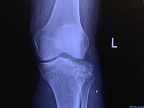

I have a brittle bone disease I was born with so a lot of fractures & surgeries because my bones tend to crumble & need to be put back together with pins, rods, screws, plates & anything else that they can come up with.

I have to agree with you about interventions, I & many others who have this disease/disorder -Osteogenesis have come to terms as you have that it seems with each surgery it feels as though it is no better especially for the pain which is caused usually by the inflammation. I have had to ask why they put so many things inside my leg/knee as I could see them sticking out & it was very uncomfortable & the surgeon said he would take them out! He said he probably put too much in me! Gee thanks! So another surgery & he tagged each thing he removed from me that he should not have placed!

Now I am reluctant to do surgeries though when they tell me my knee is crushed into a million pieces I wonder- is there a way without surgical intervention?